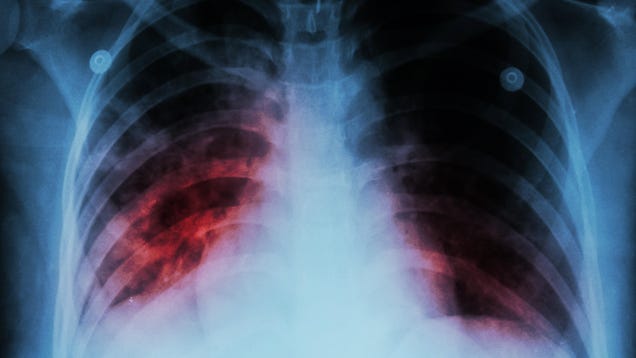

A Washington woman with tuberculosis who has refused treatment for over a year is set to be arrested as a result. According to the Tacoma-Pierce County Health Department, the woman had repeatedly disobeyed court orders to stay isolated until she completed treatment. A local judge has now issued a warrant for her…

Source: Gizmodo – Washington Woman to Be Arrested After Refusing Tuberculosis Treatment